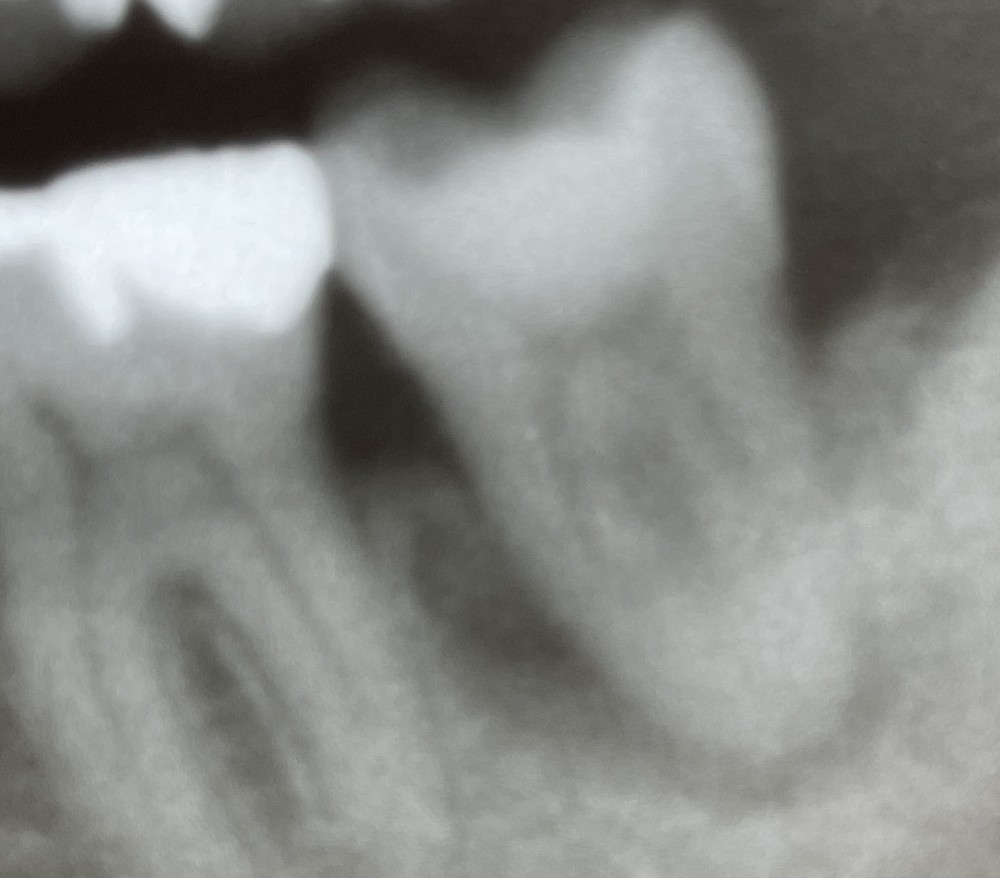

その後、2年が経過していますが、今のところ経過良好です。比較しやすいように、術前と2年経過後のエックス線写真をならべました。

(術前)